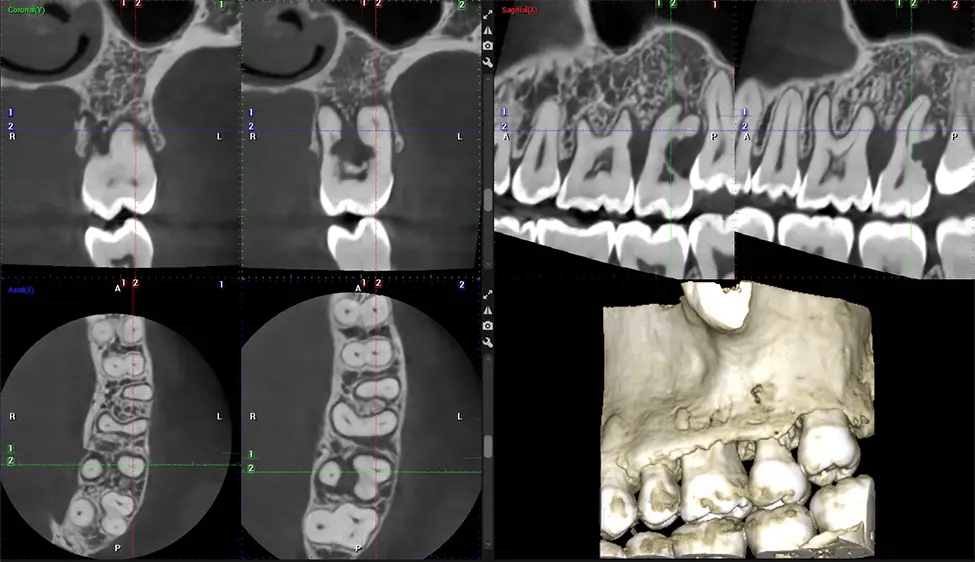

This 3D scan, called cone beam computed tomography, gives your dentist a more complete image of your oral anatomy and disease processes than a traditional X-ray. Unlike conventional X-rays, which capture a 2D image of your mouth from various angles, a 3D scan takes multiple digital X-rays for one image. It provides a complete view of your jaw, teeth, nerves, and soft tissues. This enhanced view allows dentists to detect minor issues not visible in traditional 2D scans, such as impacted wisdom teeth or bone fractures in the sinus cavity.

There are many benefits to using CBCT technology, especially compared to the traditional 2D X-ray format. One of the most significant advantages of CBCT scans is that they provide much more information than traditional X-rays. A scan lets your dentist see images from all angles of your jaw and mouth, including your sinuses, nasal cavity, cheekbones, and other surrounding areas. This added information helps your dentist craft a comprehensive treatment plan that addresses all aspects of your oral health.

Another significant benefit is that 3D imaging provides more precise images of your bone structure. These images are more detailed, providing you with a more accurate diagnosis. An accurate diagnosis means better treatment for you.

After the scanning process, the captured X-ray images are processed by the CBCT software, which applies algorithms to reconstruct a detailed 3D image of the scanned area. The software compiles these individual X-ray images and creates a digital 3D representation of the patient’s anatomy. The reconstructed 3D CBCT image can be viewed and analyzed by the dentist or radiologist. This image can be manipulated, rotated, and zoomed in or out to examine specific structures and evaluate the patient’s condition.

Planmeca Viso G7 CBCT ( Cone Beam CT Scan ) is designed to surpass the demands of industry leaders, specialists, and large institutions. It’s has a large ø25×30 cm sensor with four built-in cameras. It can capture unlimited volume sizes from a ø3×3 cm to a ø30x30cm volume capturing the skullcap through C7 on the cervical spine. The Planmeca Viso G7 offers the industry’s largest single volume scan of ø30×19 cm. It’s poised to handle advanced imaging modalities such as Planmeca ProFace® and Planmeca 4D™ Jaw Motion technology. The occipital head support allows an unimpeded view of facial tissue.

Our patented SCARA technology enables doctors to capture True Extraoral Bitewings that are as accurate at detecting caries as a 2D bitewing series, but with half the radiation dose. With our bitewings, doctors can view the apices of teeth on both jaws providing a more comprehensive view of the patients’ anatomy.